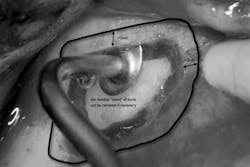

1. A full-thickness flap is reflected to gain access to the lateral wall of the maxillary sinus (Fig. 1). In this area the bone is normally very thin, usually less than 1 mm.Fig. 34. The sinus membrane is separated from the bony wall. Perforations of the membrane occur frequently during this phase. To increase safety and reduce complications, the air-driven sonic handpiece is used, coupled with the discoid insert. The insert is activated (vibrating and irrigated by the water spray) and then placed between the lateral bone wall and the Schneiderian membrane (Fig. 4).